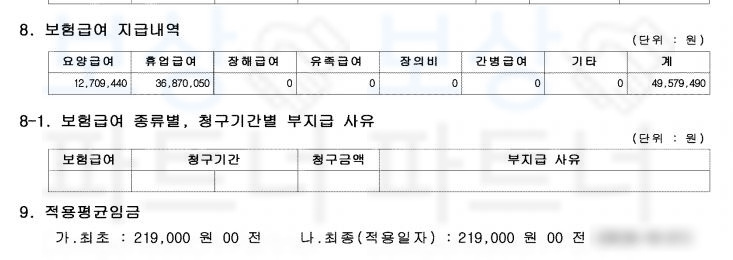

다리의 1개 관절의 단순 기능장해 **제12급 제10호 **인정받을 수 있었습니다.

산재 장해급여 33,726,000원이죠. 의뢰인은 손해보험사에 일반상해 후유 장해 항목으로 1억 원 가입되어 있으셨습니다. 보상 파트너는 피보험자의 보험 증권을 받아 가입시기 및 약관을 분석하였고 개인보험 역시도

피보험자는 고관절의 운동 장해 약간의 장해에 해당되어 5% 지급율, 영구 장해로 진단되었습니다. 보상 파트너는 대형 보험사를 상대로 피보험자의 장해를 인정받기 위해 손해 사정서 및 증빙자료를 보험사에 송부하였습니다.

물론 보험사에서는 약 2달간 평가된 장해가 과대평가되었다며 내부 의료자문을 시행하였지만 보상 파트너의 적절한 대응으로

피보험자의 후유 장애 담보 1억의 5%

총 500만 원의 후유장해보험금

지급받을 수 있었습니다.